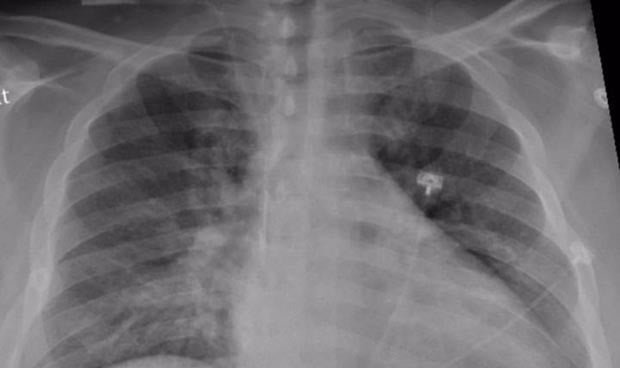

El estudio, dirigido por el neumólogo Bram van den Borst, incluyó a 124 pacientes que se habían recuperado de infecciones agudas por Covid-19. Visitaron la clínica de cuidados posteriores corona del centro médico de la universidad de Radboud, en Países Bajos. Los pacientes fueron examinados por tomografía computarizada y una prueba de función pulmonar, entre otros análisis. Después de tres meses, los investigadores hicieron un balance, que reveló que el tejido pulmonar de los pacientes se estaba recuperando bien. El daño residual en el tejido pulmonar fue generalmente limitado y se observa con mayor frecuencia en pacientes que fueron tratados en la UCI.

El investigador principal y neumólogo Bram van den Borst explica: "Los patrones que vemos en estos pacientes muestran similitudes con la recuperación después de una neumonía aguda o síndrome de dificultad respiratoria aguda (SDRA), en el que se acumula líquido en los pulmones durante mucho tiempo. Es alentador ver que los pulmones después de las infecciones por Covid-19 exhiben este nivel de recuperación", apostilla.

"Sin embargo, parece que hay un subgrupo claro de pacientes que inicialmente experimentaron síntomas leves de Covid-19 y luego siguieron experimentando quejas y limitaciones persistentes a largo plazo --explica Bram van den Borst--. Lo sorprendente es que apenas encontramos anomalías en los pulmones de estos pacientes. Considerando la variedad y gravedad de las quejas y el tamaño plausible de este subgrupo, existe una necesidad urgente de realizar más investigaciones sobre las explicaciones y las opciones de tratamiento".